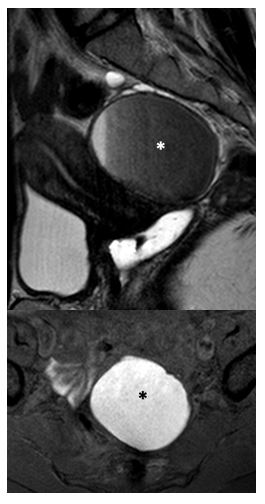

Fig 6 Nodule du LUS gauche

• IRM coupe axiale T2

• IRM coupe sagittale T2

• IRM coupe axiale T1FS

Nodule du ligament utéro sacré gauche, avec implants hémorragiques, et adhérences digestives